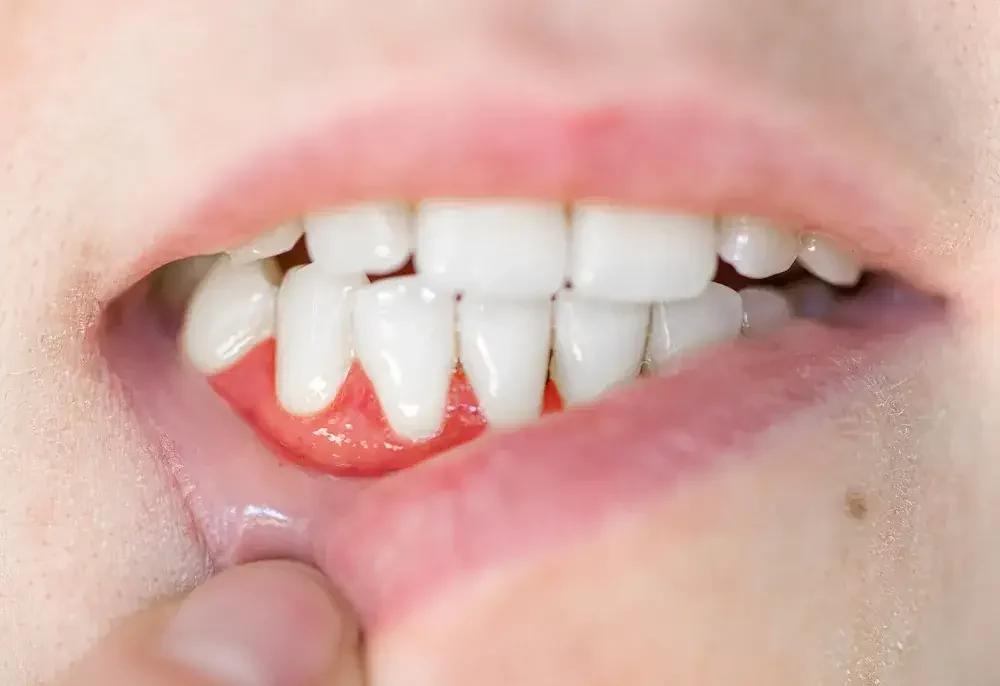

Selain nyeri, pembengkakan pada area gusi yang terinfeksi juga merupakan gejala yang umum pada abses gusi. Gusi di sekitar gigi yang terinfeksi akan membengkak dan terasa lembut saat disentuh.

Biasanya, pembengkakan ini disertai dengan perubahan warna gusi yang menjadi lebih merah atau bahkan merah gelap, menandakan adanya peradangan.

Gusi yang bengkak bisa mempengaruhi kenyamanan saat berbicara atau makan, dan pembengkakan yang parah bisa membuat bagian dalam mulut terasa penuh atau terhalang.